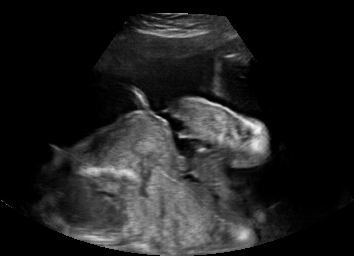

US simulation. We used a ray-tracing framework to render B-mode images from a geometric fetal model, by simulating a convex probe placed at multiple locations and orientations on the abdominal surface, with imaging settings listed in Tab 1. At each location, simply rasterizing a cross-section through the triangulated anatomical surfaces at the ultrasound center imaging plane provided corresponding semantic maps. Fig. 3 shows example B-mode images with corresponding semantic maps. A total of simulated frames were resized to and randomly split into training-validation-test sets by 80-10-10%.

In Fig. 3 we show that only learning an auxiliary seg-to-real translation, i.e. CUT+S, cannot guide the network to learn the semantics of simulated images.

CUT+SC with the loss term largely reduces hallucinated image content, although it still fails to generate fine anatomical details. With the multi-domain conditional generator and additional losses of ConPres, translated images preserve content and feature a realistic appearance. Training without leads to training instability.

Comparison to state-of-the-art. As seen qualitatively from the examples in Fig. 3, our method substantially outperforms the alternatives in terms of content preservation, while translating realistic US appearance. CycleGAN, SASAN, and CUT hallucinate inexistent tissue regions fail to generate fine anatomical structures, e.g. the ribs. StarGAN fails to generate faithful ultrasound speckle appearance, which leads to highly unrealistic images. Our method ConPres preserves anatomical structures, while enhancing the images with a realistic appearance. It further faithfully preserves acoustic shadows, even without explicit enforcement. However, as seen from the last column, the refraction artefact appears artificial in the images translated by all the methods. Note that although the imaging field-of-view (FoV) and probe opening in the simulation is significantly different from the real in-vivo images (Fig. 2) used for training, our ConPres maintains the input FoV closely compared to previous state-of-the-art. The results in Tab 2 quantitatively confirm the superiority of our method. Note that SSIM and FID/KID are used to measure translation performance from two different and sometimes competing aspects, with the former metric for quantifying structure preservation and the latter metrics for image realism.